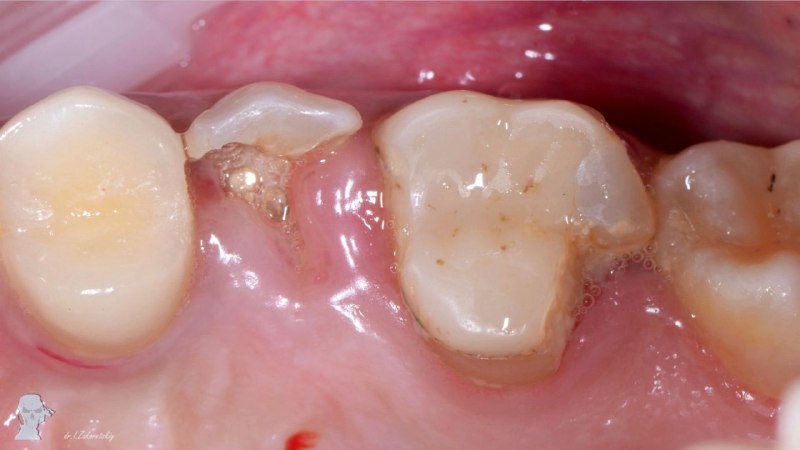

✨Когда все сказали, шансов нет, но мы их переубедили. Особое внимание на десну и ее состояние спустя 4 года. Экструзия 5 го, изоляция глубокого дефекта 6го, эндо перелечивание, Вертикальное препариров

7 мар. 2026 г.

2.8k 57 14